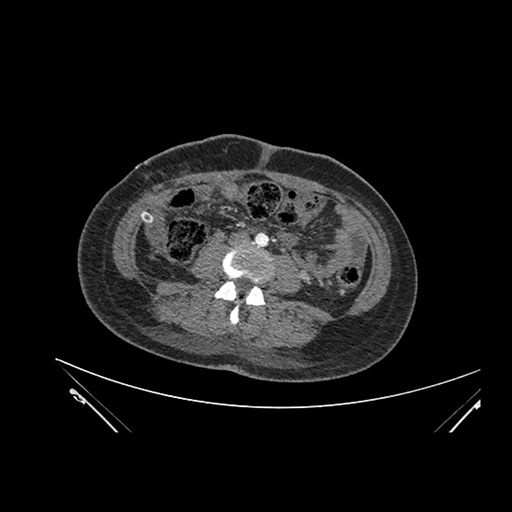

Imaging Analysis

Look through the patient's CT scan to identify any areas of concern for the necessary procedure.

Axial Venous

Based on initial findings, which issue(s) would you be most concerned about?